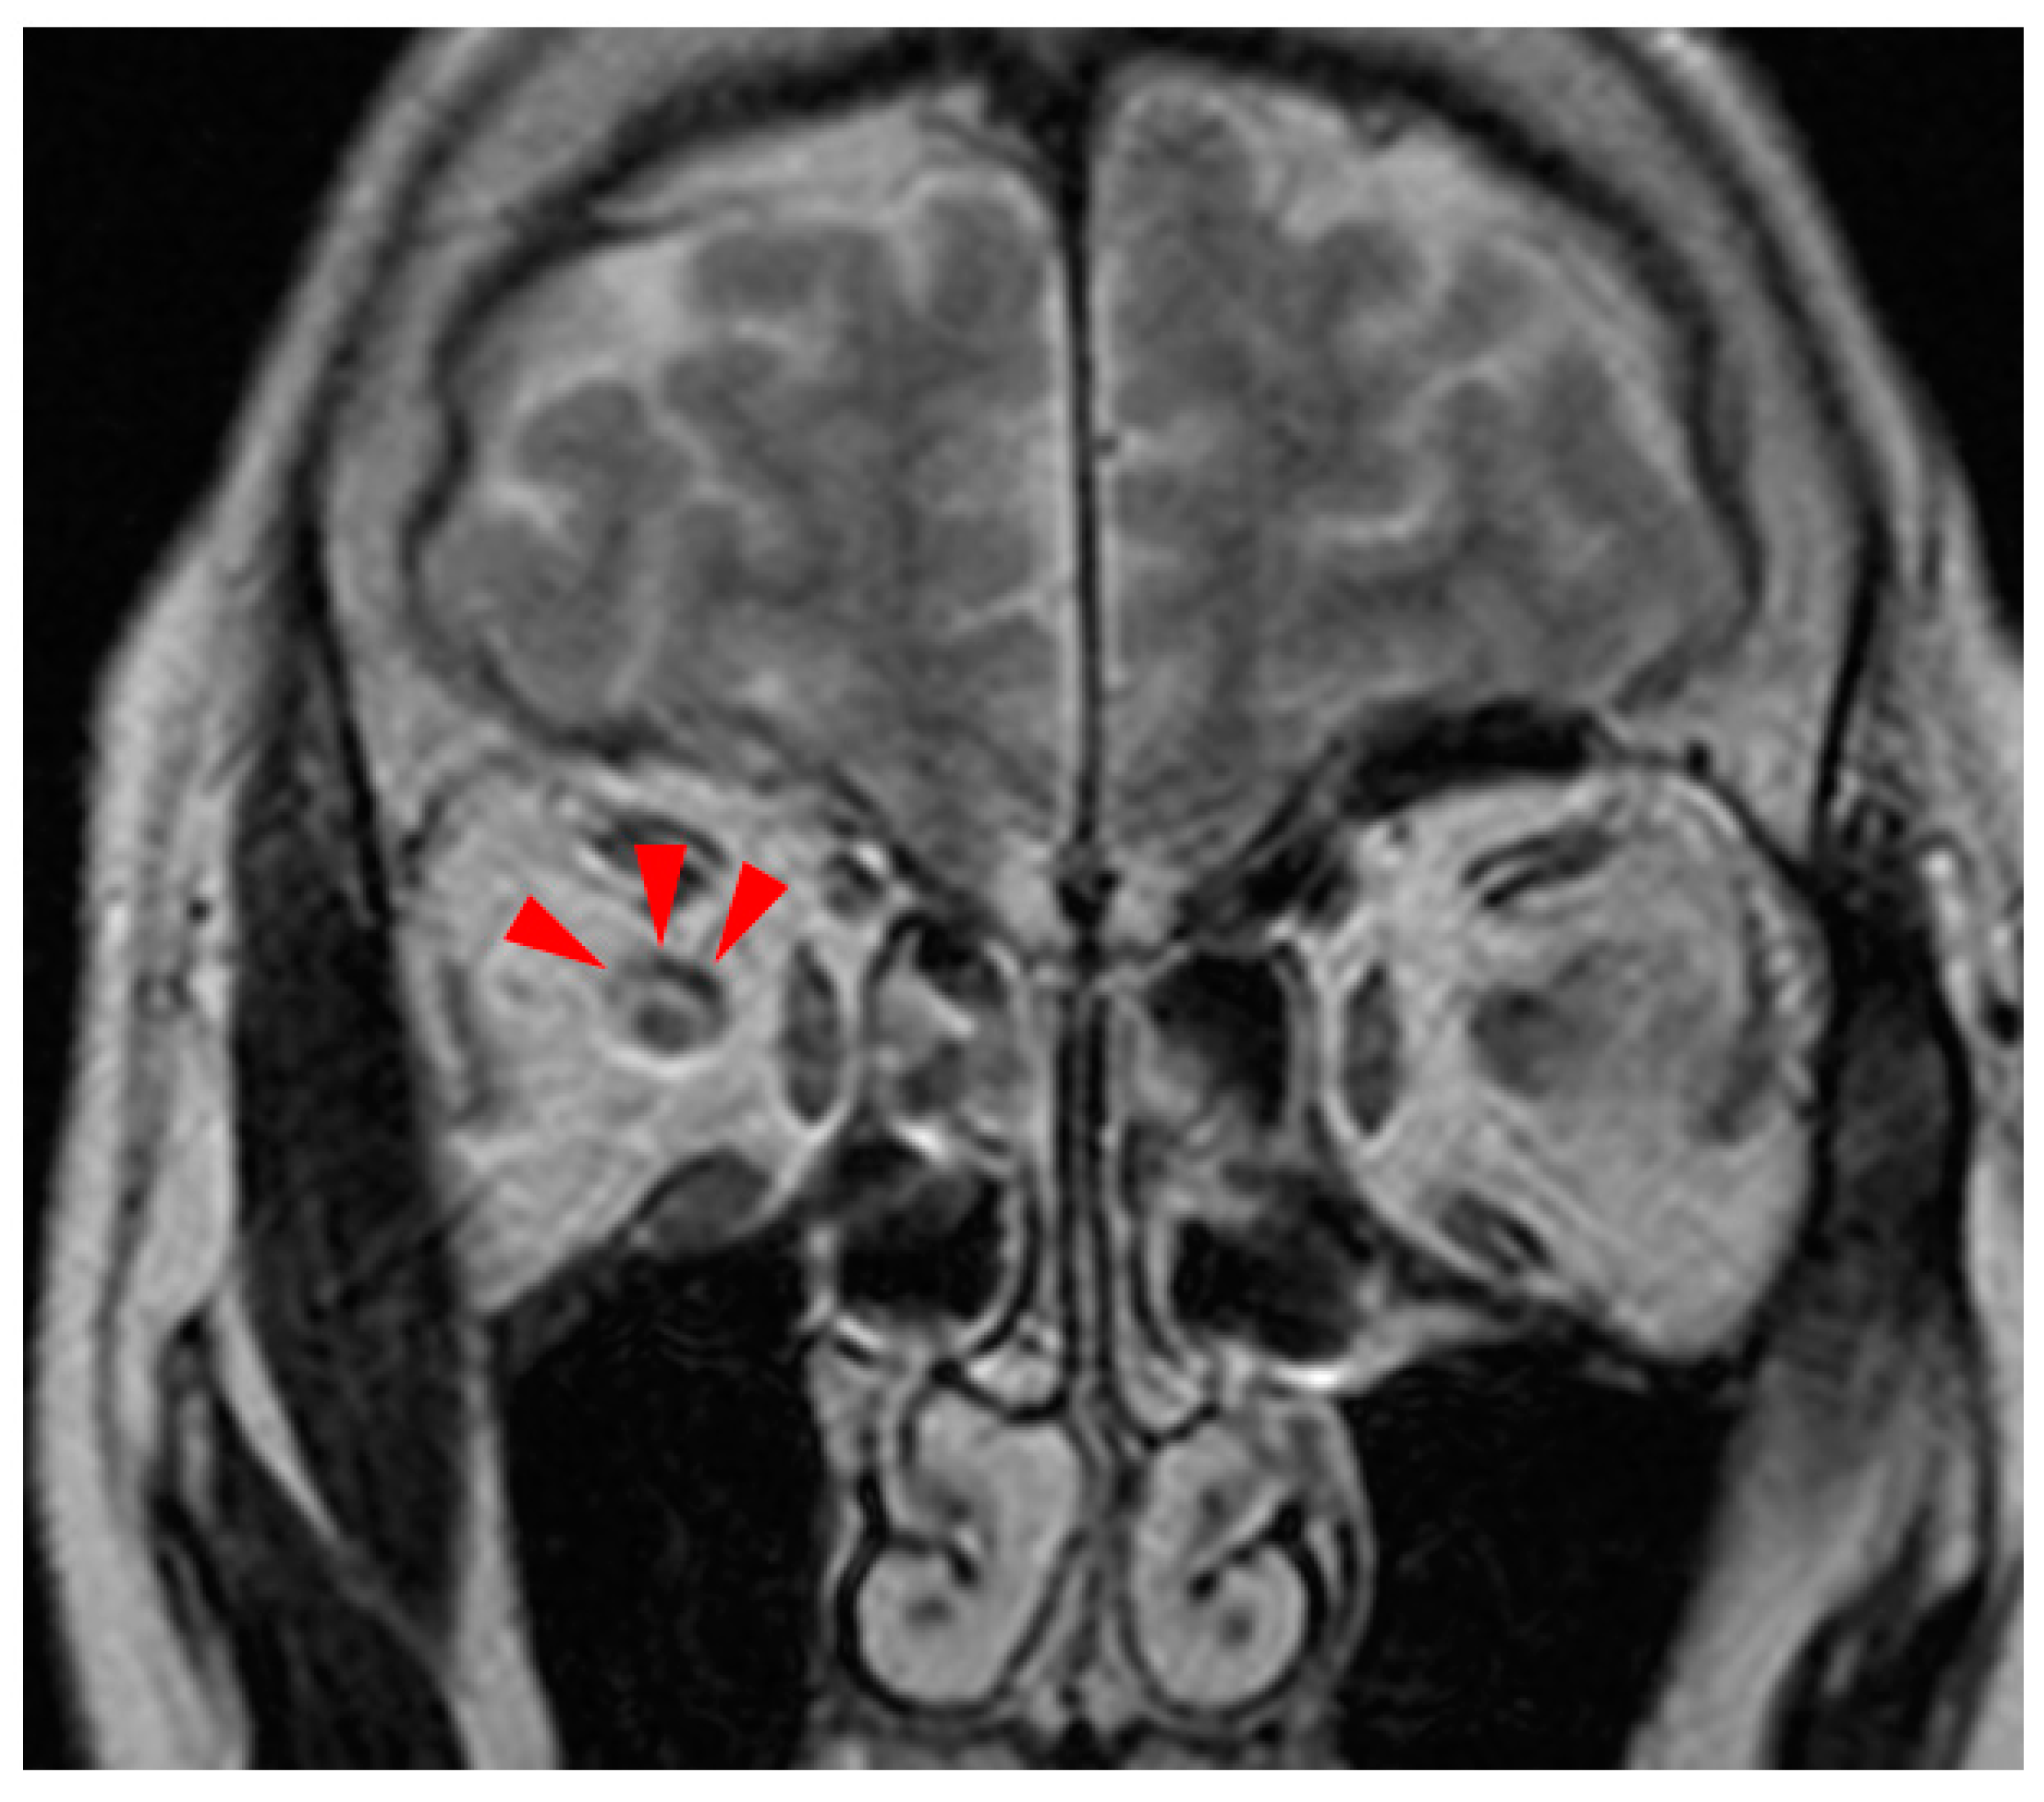

2. Case Presentation